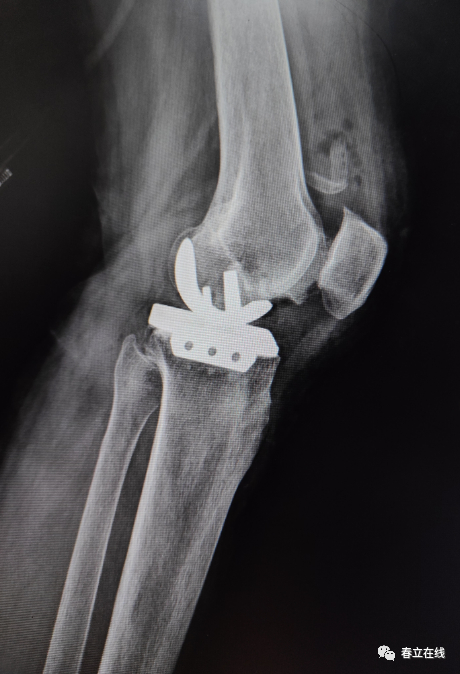

术后片